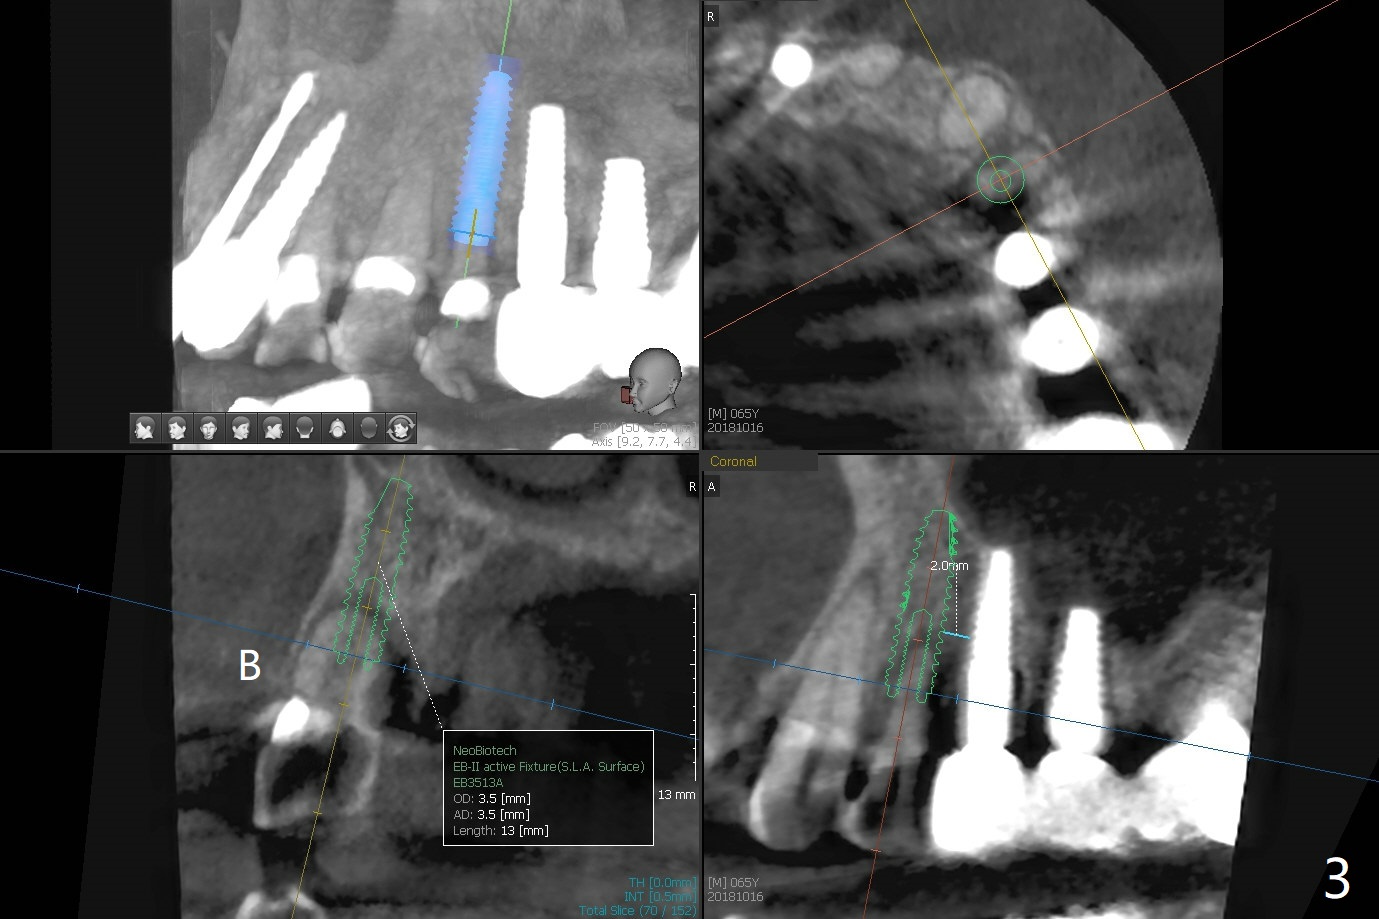

A 66-year-old man agrees to extract #12 for implant immediate post #10 implant crown cementation (Fig.1). Because of the narrow mesiodistal space, either a 1-piece (Fig.2) or 3.5 mm 2-piece (Fig.3) implant will be placed.